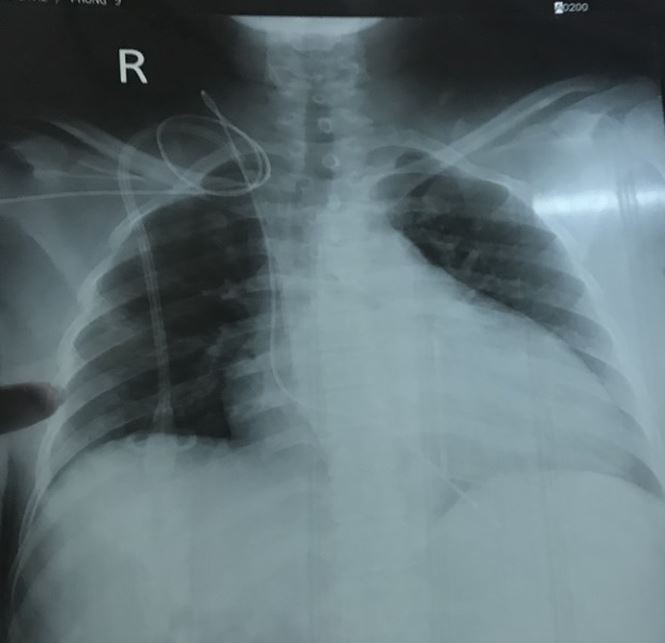

Điện tim trước khi đặt máy tạo nhịp tạm thời |

Trong quá trình tiến hành thủ thuật đặt máy tạo nhịp tim tạm thời, các bác sĩ ghi nhận rất khó tiếp cận tĩnh mạch để đưa dây điện cực tạo nhịp vào tim do catheter lọc thận lâu ngày làm hẹp đường vào tĩnh mạch chủ trên. Sau một thời gian cố gắng và kiên trì, các bác sĩ cũng đã đặt thành công máy tạo nhịp tim tạm thời để cứu mạng BN. Tuy nhiên về lâu dài, BN này có chỉ định để đặt máy tạo nhịp tim vĩnh viễn.

Sau khi đặt máy tạo nhịp tim |